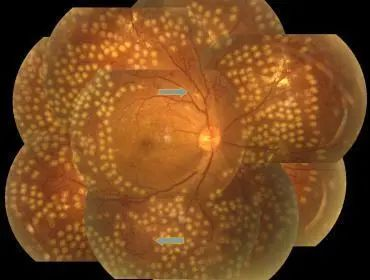

3、散開瞳孔看眼底和眼底照相:看清整個視網(wǎng)膜的狀況,也可用于記錄病變的進展嚴重程度;

4、眼底熒光血管造影(FFA):如果發(fā)現(xiàn)患者眼底出血滲出,建議患者做熒光血管造影,了解我們?nèi)庋劭床怀鰜淼?,如是否長了新生血管,是否有很多血管都閉塞了,從而選擇治療方案;

2、視網(wǎng)膜激光光凝:采用激光的熱凝效用,在局部出血部位和(或)無灌注區(qū)形成凝固激光斑,達到止血、預防再出血的效果。是有效降低重度非增生型和增生型患者嚴重視力損傷的主要治療方法,早期的全視網(wǎng)膜光凝能有效預防失明。